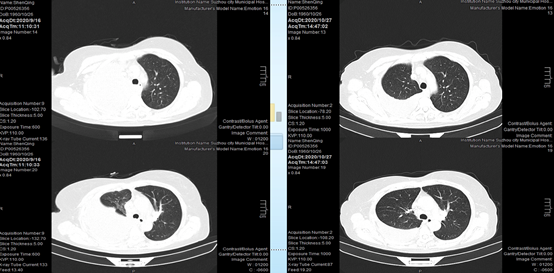

2020-10-27,CT复查提示患者胸水较前稍有减少,但仍持续存在。

此次治疗后,患者自行咨询美国MD安德森医生,要求更换治疗方案为,全脑放疗,行胸膜固定术,继续奥希替尼80mg qd。